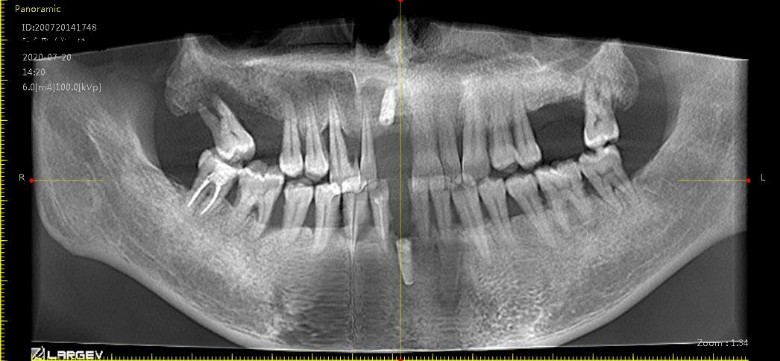

我有两颗定时炸蛋一样的智齿,几年了没勇气去拔 [复制链接]

尽快处理,我家娃智齿也是这样横躺,已经顶到前面的牙齿了,去了上海九院,昆山二院,昆山同济口腔医院,每个医生给出的方案都不一样,今年过年寒假把2颗都拔了,主要顶到前面牙齿,前面牙齿长歪了。花了5K ,不好拔,横躺着还没出牙龈。

我的大牙全部智齿顶坏了!